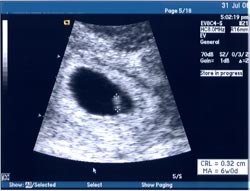

This is now 2 weeks old, so I'm at least 8 weeks along. Here's the proof.

Click on the image for a larger version.

There was some discrepancy between when I said my last period was and the results of the ultrasound. Based on my last period, my due date would be about March 18, but with ut said March 26. So I'm due sometime around there.